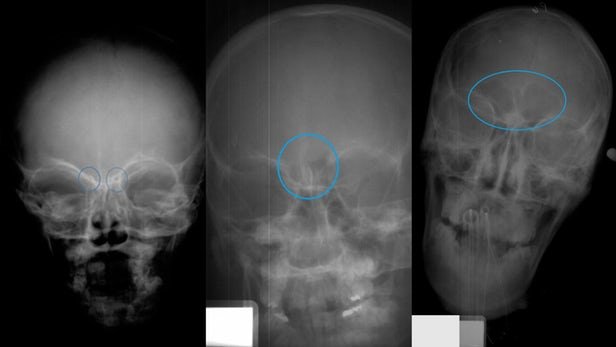

تعیین سن کودکان از روی سینوس آنها!

ICTPRESS - انسان شناسان، آسیب شناسان و سایر دانشمندان به زودی به ابزاری دسترسی پیدا خواهند کرد که به واسطه آن می‌توان سن کودکان فوت شده را بر اساس بقایای اسکلت آنها تشخیص داد.